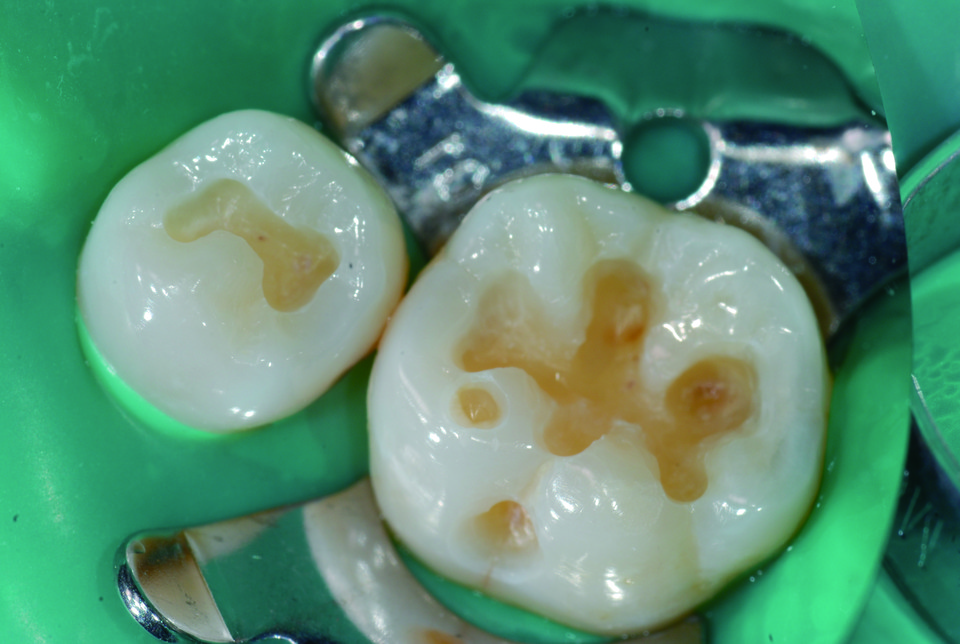

또 High Flow는 base 외에 교정 retainer 의 부착, 실란트 등 치료에도 활용 가능합니다. 방사선 불투과성이 높기 때문에 방사선상에서 우식과 구분이 쉽게 가능하며 2.0 & 0.7µm 와 20nm의 다양한 크기의 필러를 함유함으로써 내마모도에도 강한 모습을 보이기 때문에 구치부 수복에도 유용합니다. (그림7~11)